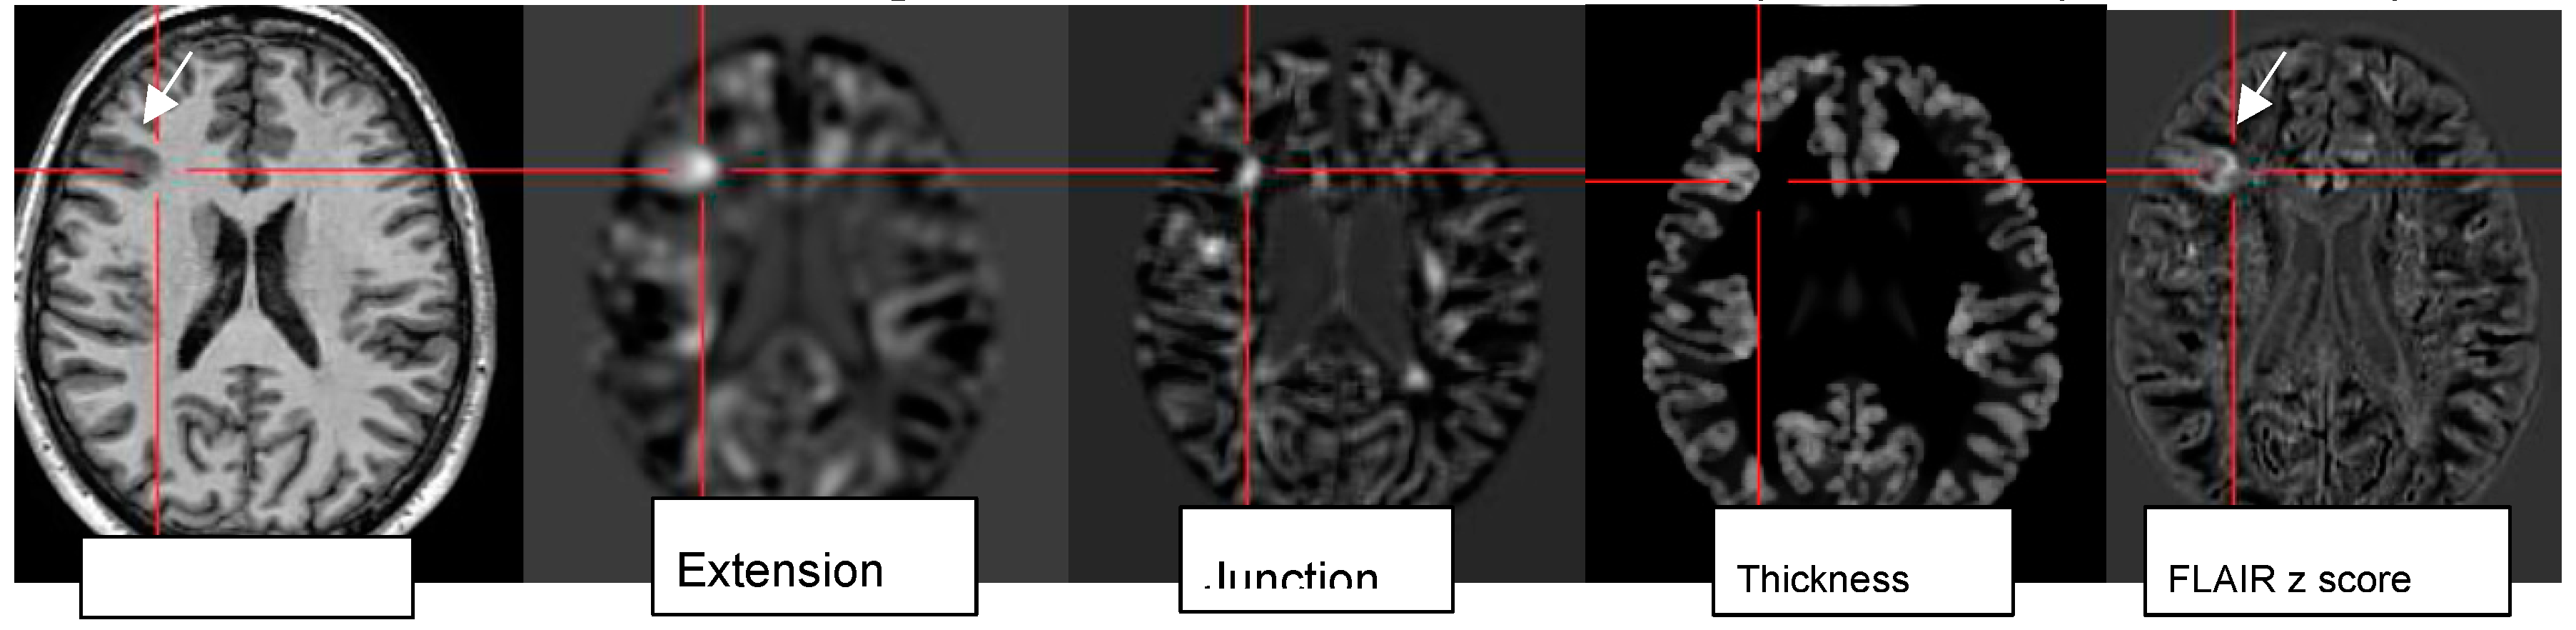

4.7. Postprocessing by Quantitative Analysis of Signal Intensity, Volumetry Enhances Temporal Lesion Identification